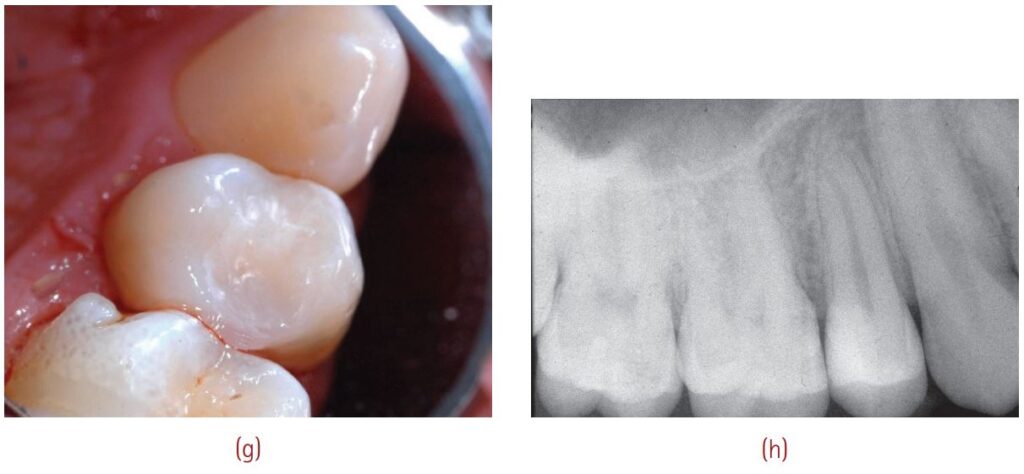

Hình 10.14 dưới đây mô tả một ca che tủy trực tiếp bằng Biodentine.

Nguồn: Grossman’s Endodontic Practice – B. Suresh Chandra, V. Gopikrishna.